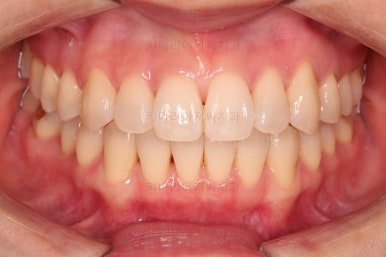

장치를 사용한지 1년 2개월째 사진입니다.

매우 가지런해졌죠.

보통 부산인비절라인은 풀세트로 3회가량 하게 되는데요.

이번 환자분은 1회로도 이 정도의 결과를 만들어 냈습니다.

이 정도의 느낌도 나쁘지는 않지만 미세하게 수정할 부분들이 보여 1회 더 제작하기로 했습니다.

1회 치료를 마친 시점의 얼굴모습인데요.

입매는 그대로이며 치열도 고르고 중앙선도 많이 좋아졌습니다.